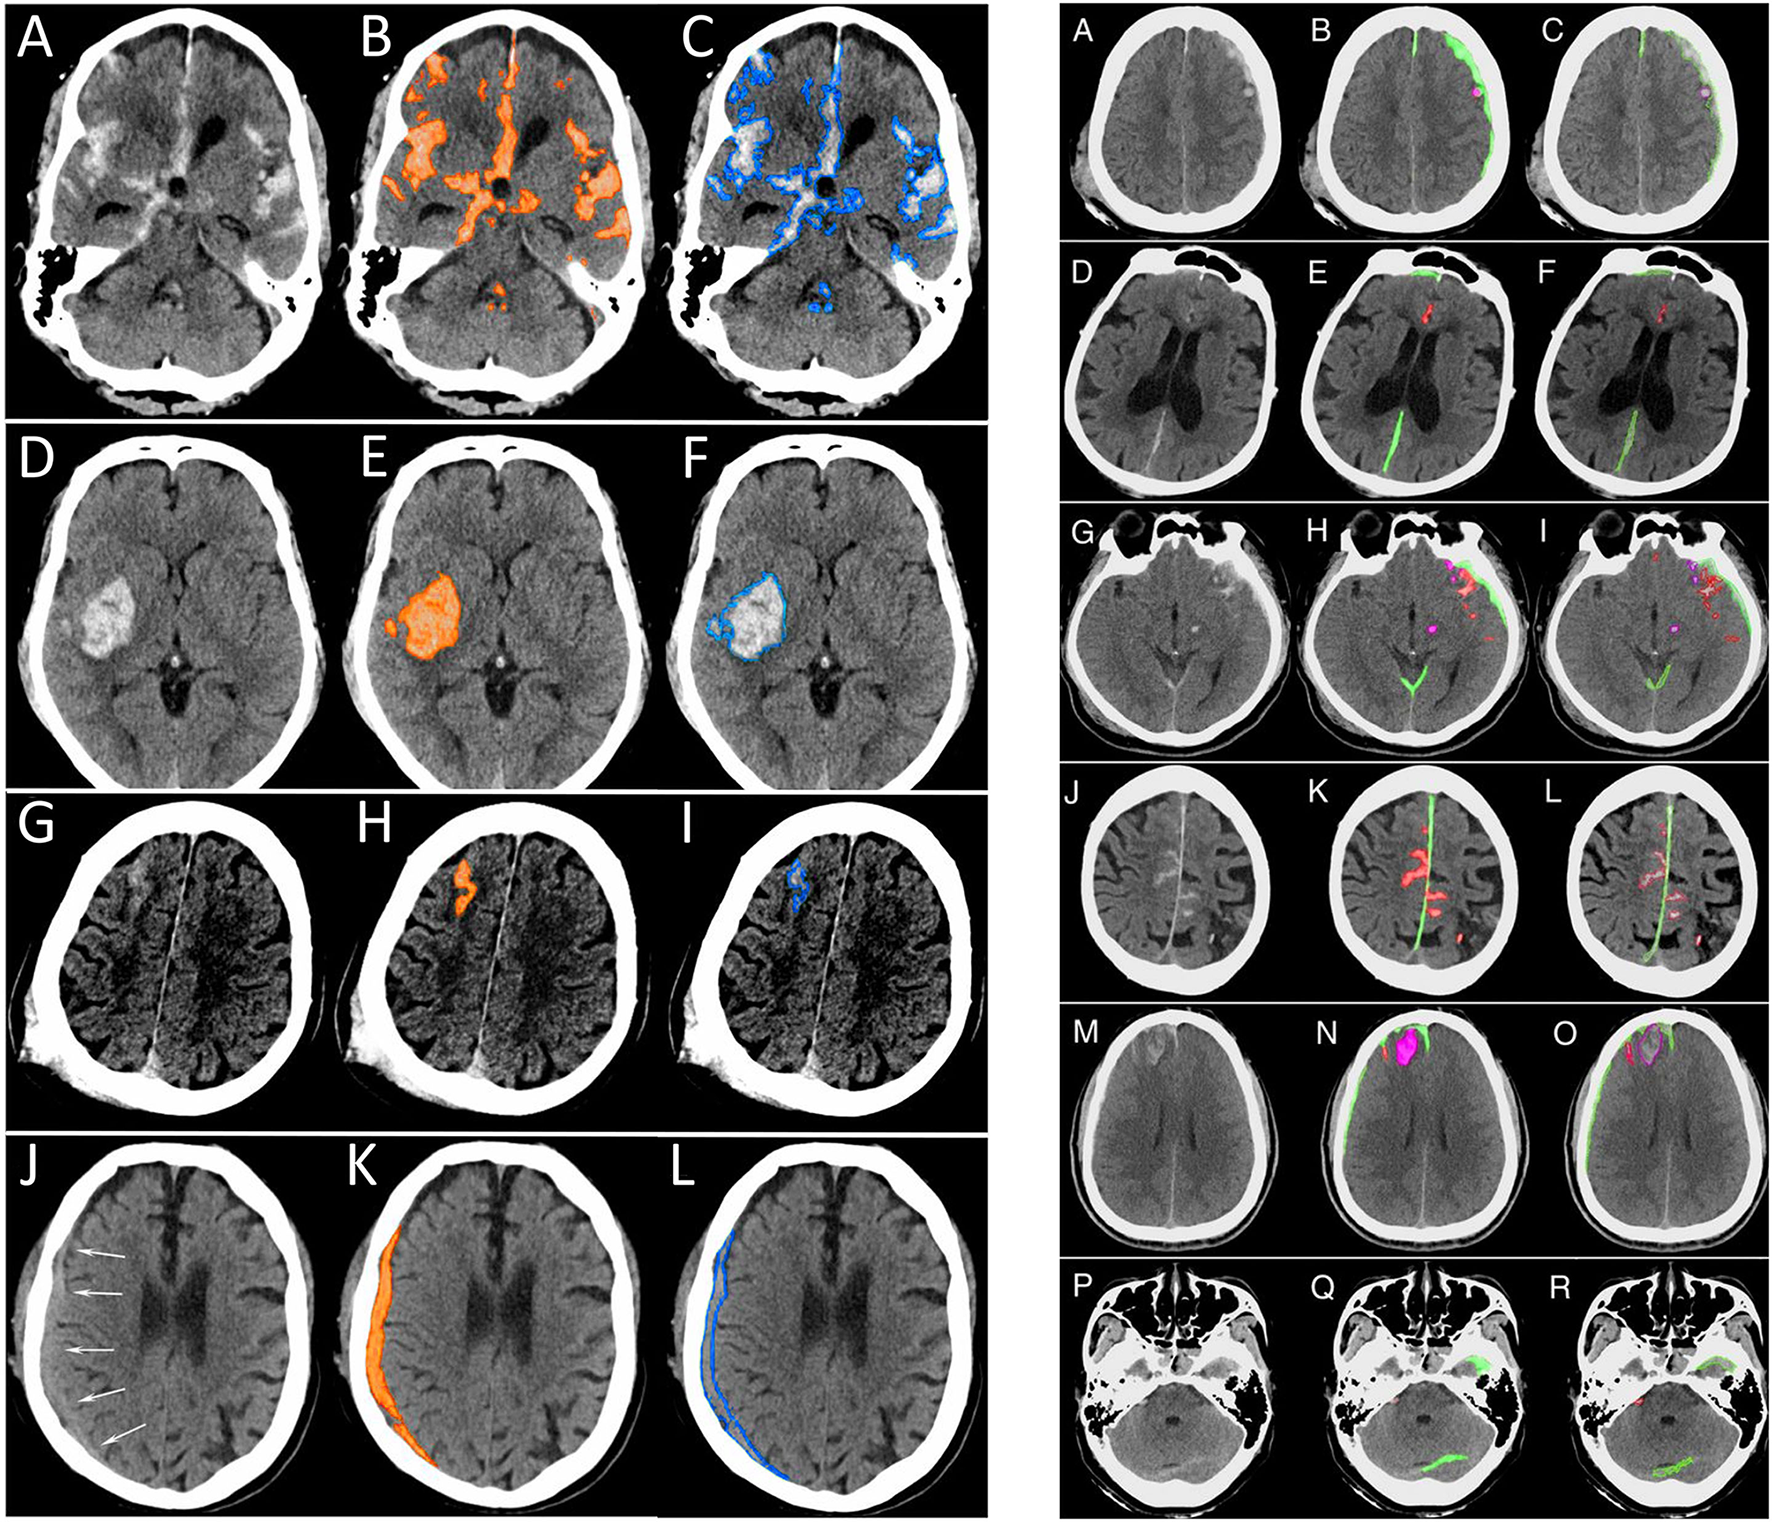

Kuo et al. (29) used a different approach, training a deep learning model on CT exams with hemorrhage labeled at the pixel level. The authors developed a patch-based fully convolutional neural network, which was optimized to perform joint classification and segmentation of intracranial hemorrhage. The algorithm had an identical input-output pairing (i.e., input training data and output prediction data with identical granularity of the labels). Training data consisted of 4,396 pixel-labeled CT exams. Rather than outputting heatmaps with diffuse boundaries, as seen with the Lee et al. study, this algorithm's segmentations provide high-resolution localization information (Figure 10, left panel). The classification performance was benchmarked against four radiologists on an independent evaluation set, in which the network outperformed two of the four radiologists, achieving an AUC of 0.991 for the classification task and a Dice coefficient of 0.75 for the segmentation task. An exploratory multiclass study was also conducted, in which the model identified and segmented different hemorrhagic subtypes. Segmentation visualizations from the multiclass study were also shown (Figure 10, right panel). This study was important because it included a broad selection of visualization examples, demonstrating detailed intracranial hemorrhage segmentations of intracranial hemorrhage and its subtypes. However, this approach requires a dataset annotated at the pixel level, which is highly time-consuming, expensive to obtain because it requires highly-trained human experts, and difficult to scale. Despite this, the study demonstrated the potential for deep learning algorithms to achieve expert-level classification performance and excellent segmentation, provided densely annotated data are available.

Figure 10

Examples of intracranial hemorrhage detection, classification, and segmentation by a convolutional neural network (CNN) (29). (Left) Binary segmentations, in which the model indicates the presence or absence of intracranial hemorrhage only. (A,D,G,J). The first column shows the original head CT images. (B,E,H,K) The middle column shows the same images with orange shading of pixel-level probabilities >0.5 for intracranial hemorrhage as determined by the CNN. (C,F,I,L) The third column shows the original images with a blue outline drawn by an expert neuroradiologist around all areas of intracranial hemorrhage. (Right) Multiclass segmentations, in which the model not only detects intracranial hemorrhage but additionally indicates the hemorrhage subtype. (A,D,G,J,M,P) The first column shows original head CT images. (B,E,H,K,N,Q) The second column shows the algorithm's predictions. Each subtype is indicated by a different color, where subdural hematoma is green, brain contusion is purple, and subarachnoid hemorrhage is red. (C,F,I,L,O,R) The third column shows the “ground truth” labels drawn by expert neuroradiologists.